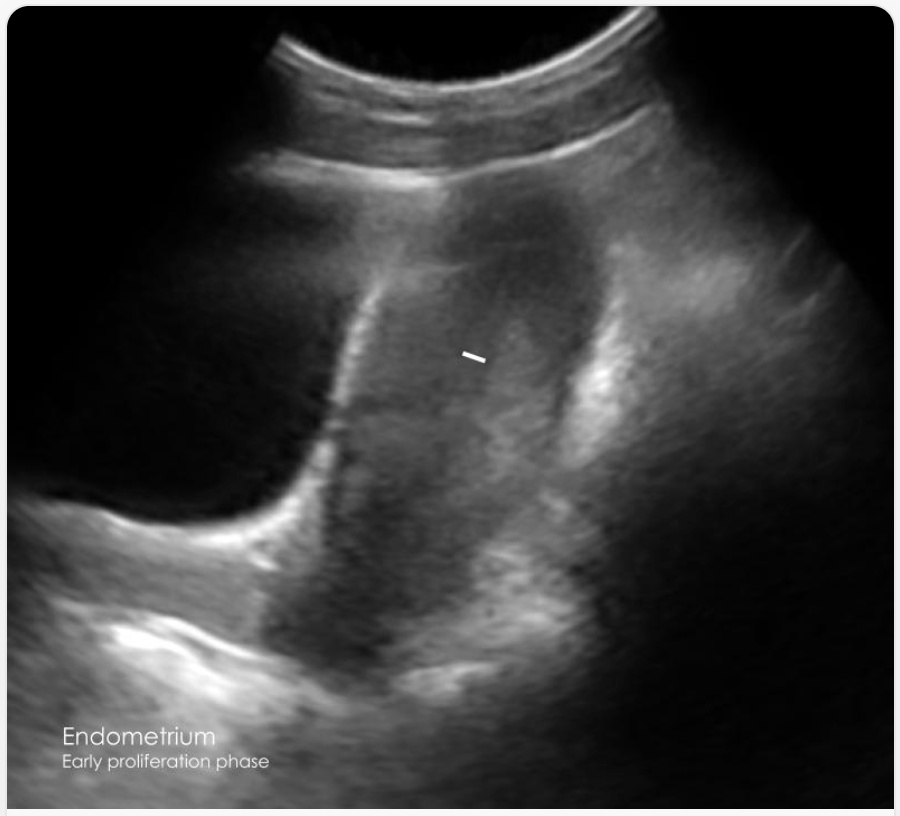

Uterine lining ultrasound

Uterus & Endometrium

Uterine lining — thin and smooth

Normal

Your uterus is a healthy size and shape. There are no signs of common growths like fibroids or adenomyosis. The lining of your uterus (the endometrium) looks smooth and thin, exactly what we expect to see at this stage of your cycle.